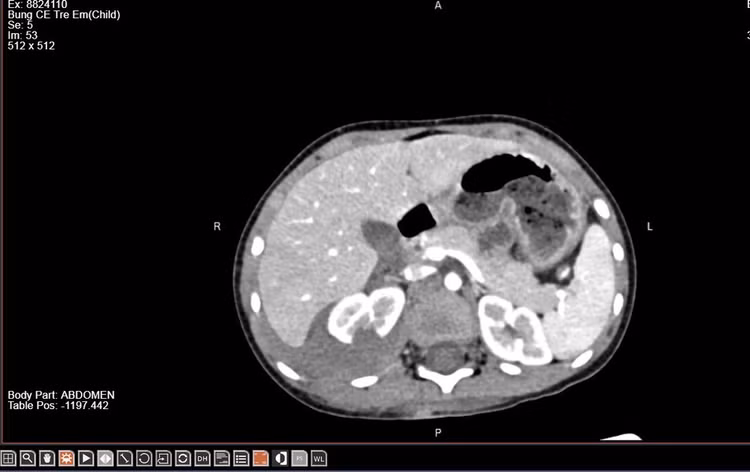

Trẻ được chỉ định thực hiện chụp cắt lớp vi tính ổ bụng có tiêm thuốc cản quang để đánh giá mức độ tổn thương thận. Kết quả cho thấy thận phải vỡ làm 2 mảnh, có thoát thuốc ra khoang quanh thận. Bác sĩ kết luận trẻ bị chấn thương thận phải độ IV theo ASST (bảng phân loại chấn thương thận của Hiệp hội Phẫu thuật Chấn thương Mỹ).

| Hình ảnh vỡ thận trên phim chụp - Ảnh BVCC |